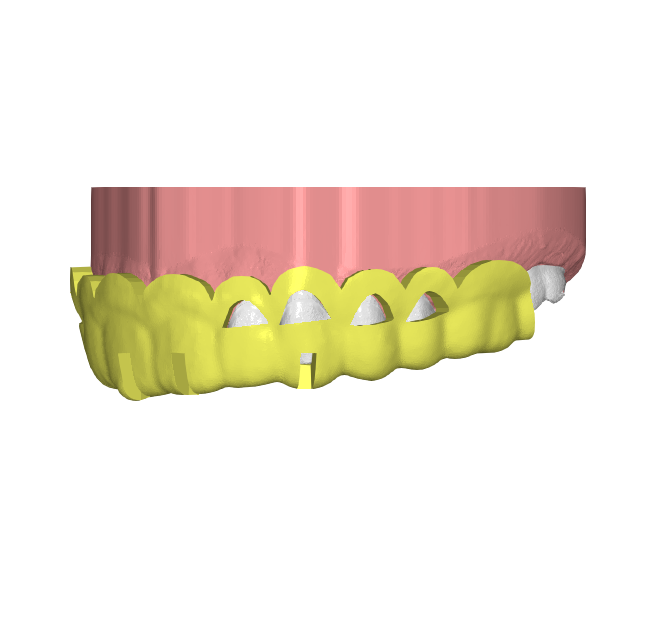

A) Los archivos no son ideales, pero podemos trabajar con ellos: le informaremos de cualquier limitación, y aun así recibirá su diseño dentro del plazo establecido

B) No podemos trabajar con los archivos proporcionados: en Elevantia Solutions priorizamos la calidad y la excelencia en cada proyecto. Si las fotografías no cumplen con los requisitos, los archivos STL están incompletos o el registro de mordida es inexacto, no podremos proceder con el caso. Si esto ocurre, pausaremos el proceso, nos pondremos en contacto contigo y esperaremos archivos actualizados para continuar